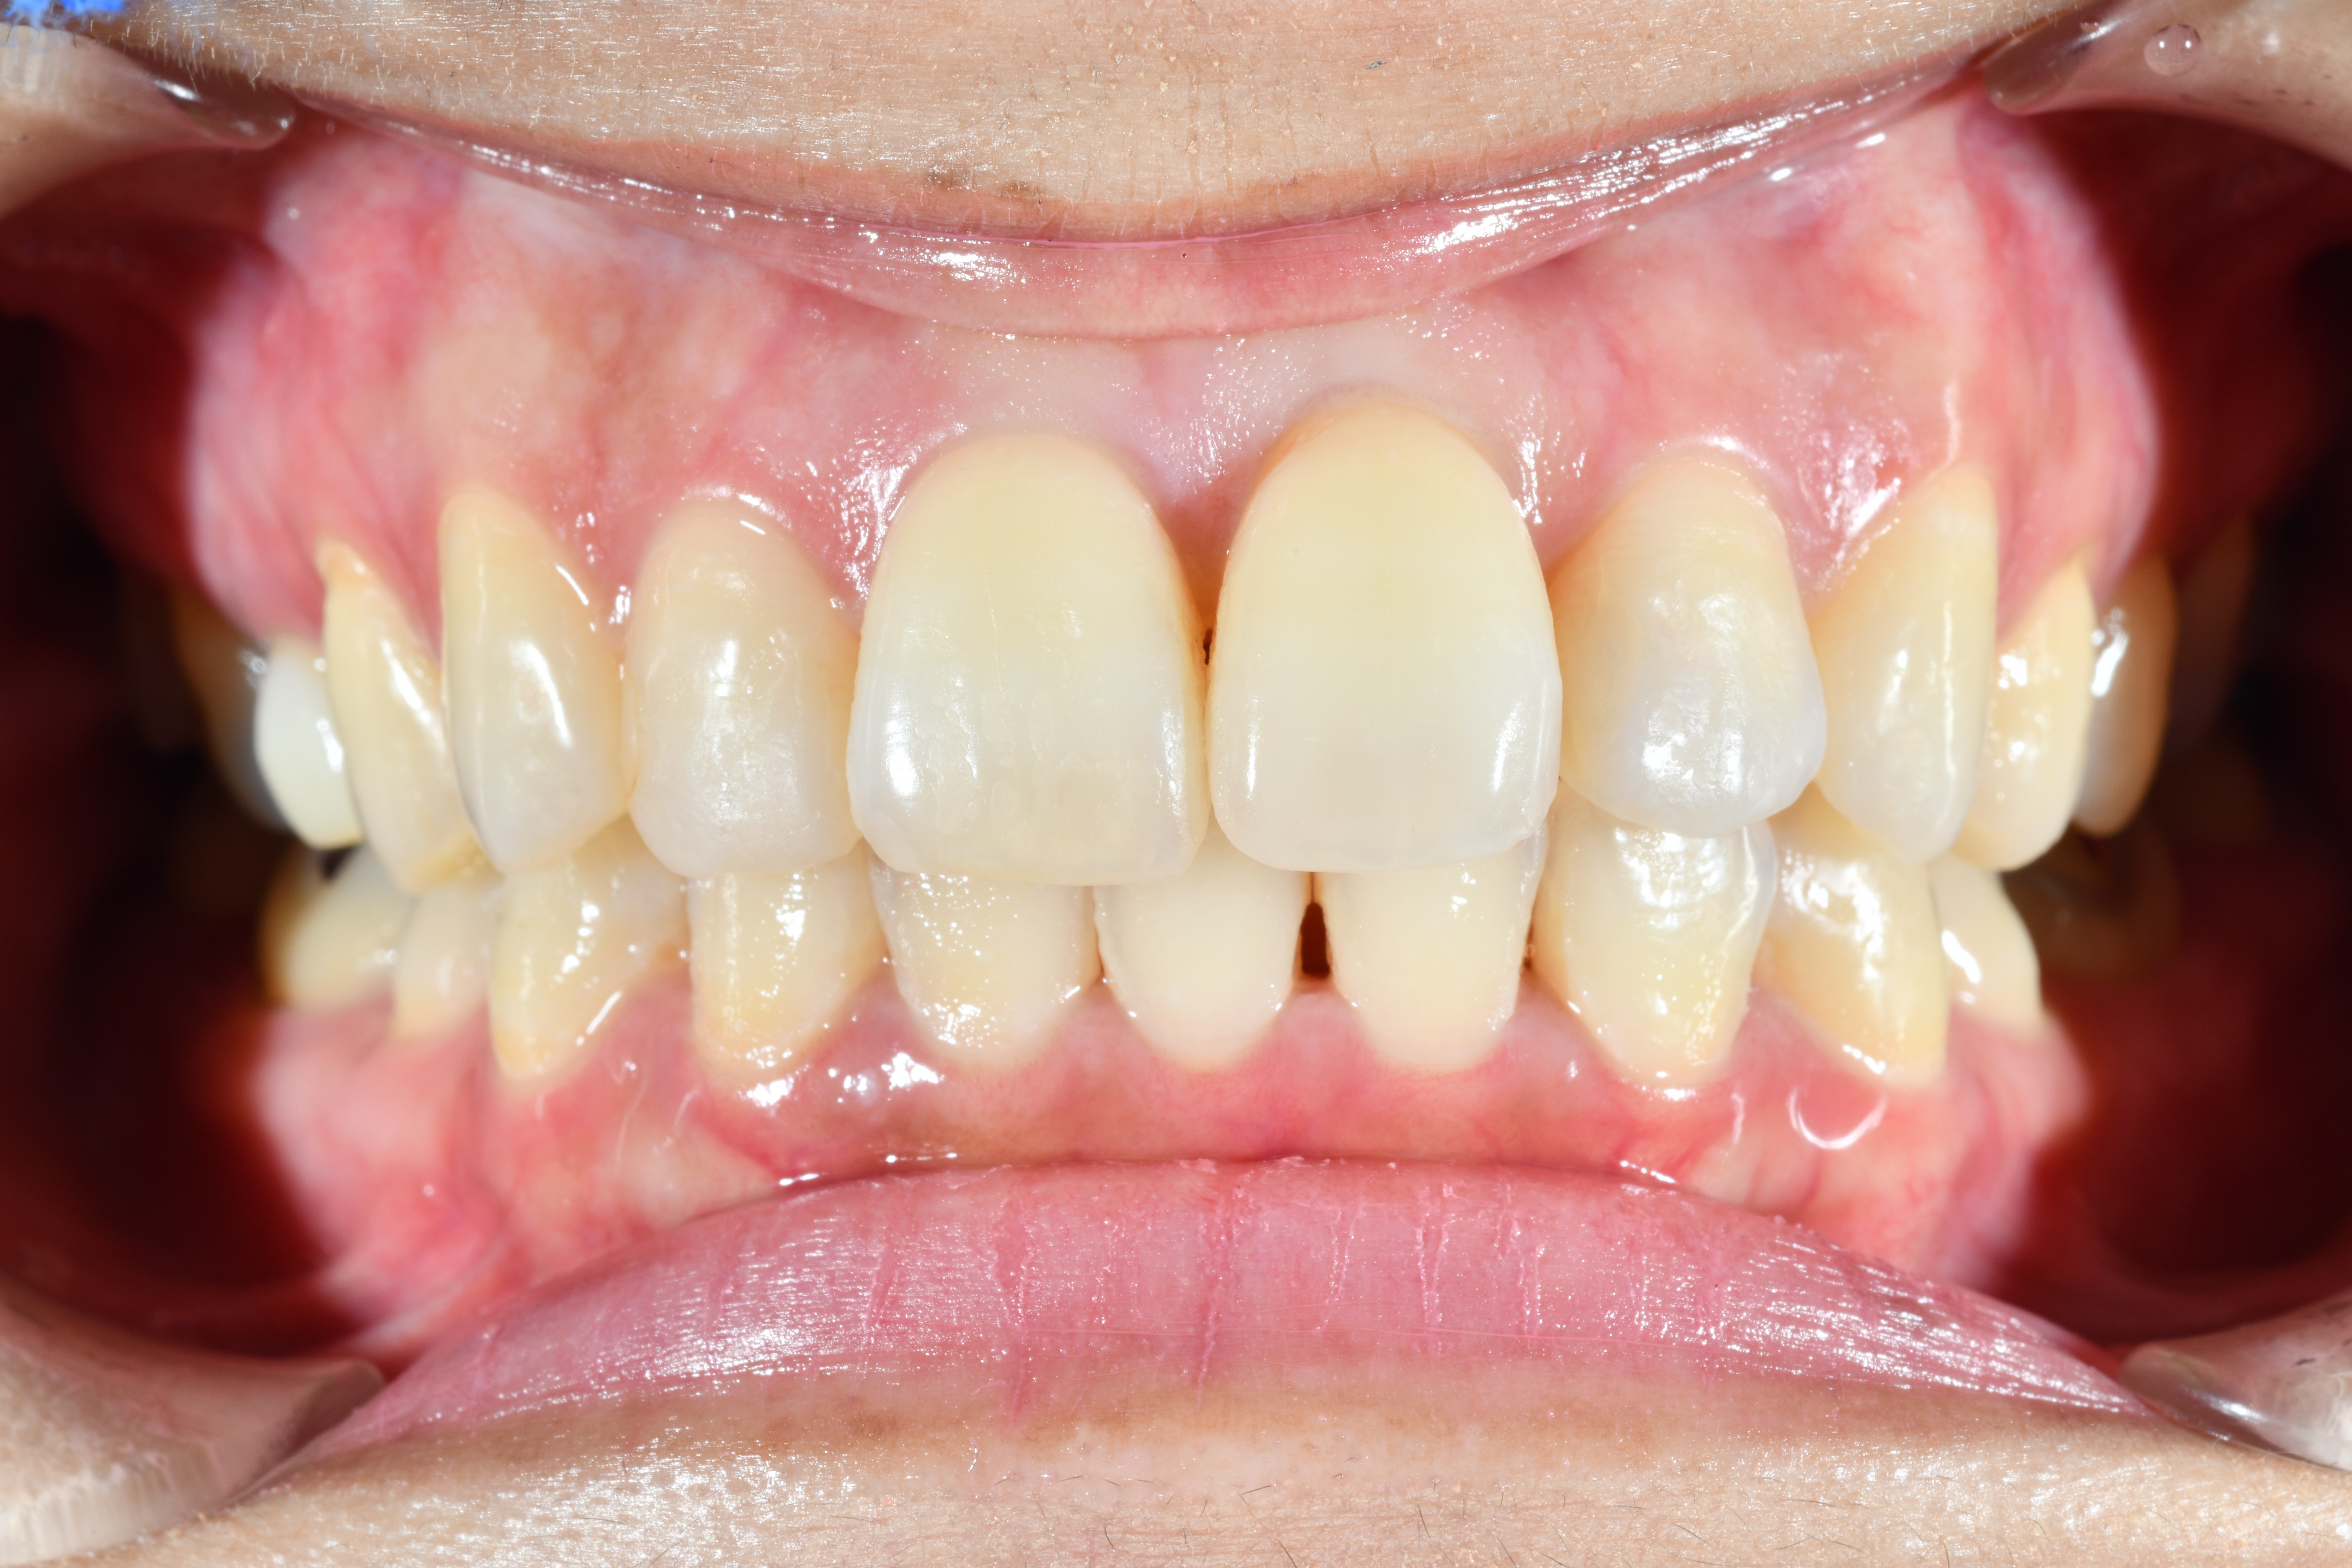

毎週自分で歯並びの写真を撮っていたので日々綺麗になっていく歯並びを見るのが嬉しく、家族からも綺麗になったねと言われました! マウスピース矯正と並行してホワイトニングも行っていたので、歯が格段に綺麗になるのを実感できたのが嬉しかったです。

痛みも少なく、マウスピースをしていても目立たないですし、私が始める前に思っていたよりもずっと短い期間で矯正が終わりました。通院も最低限で済むので、ストレスなく過ごすことができました。スマイルモアで矯正をして、本当に良かったと思っています。